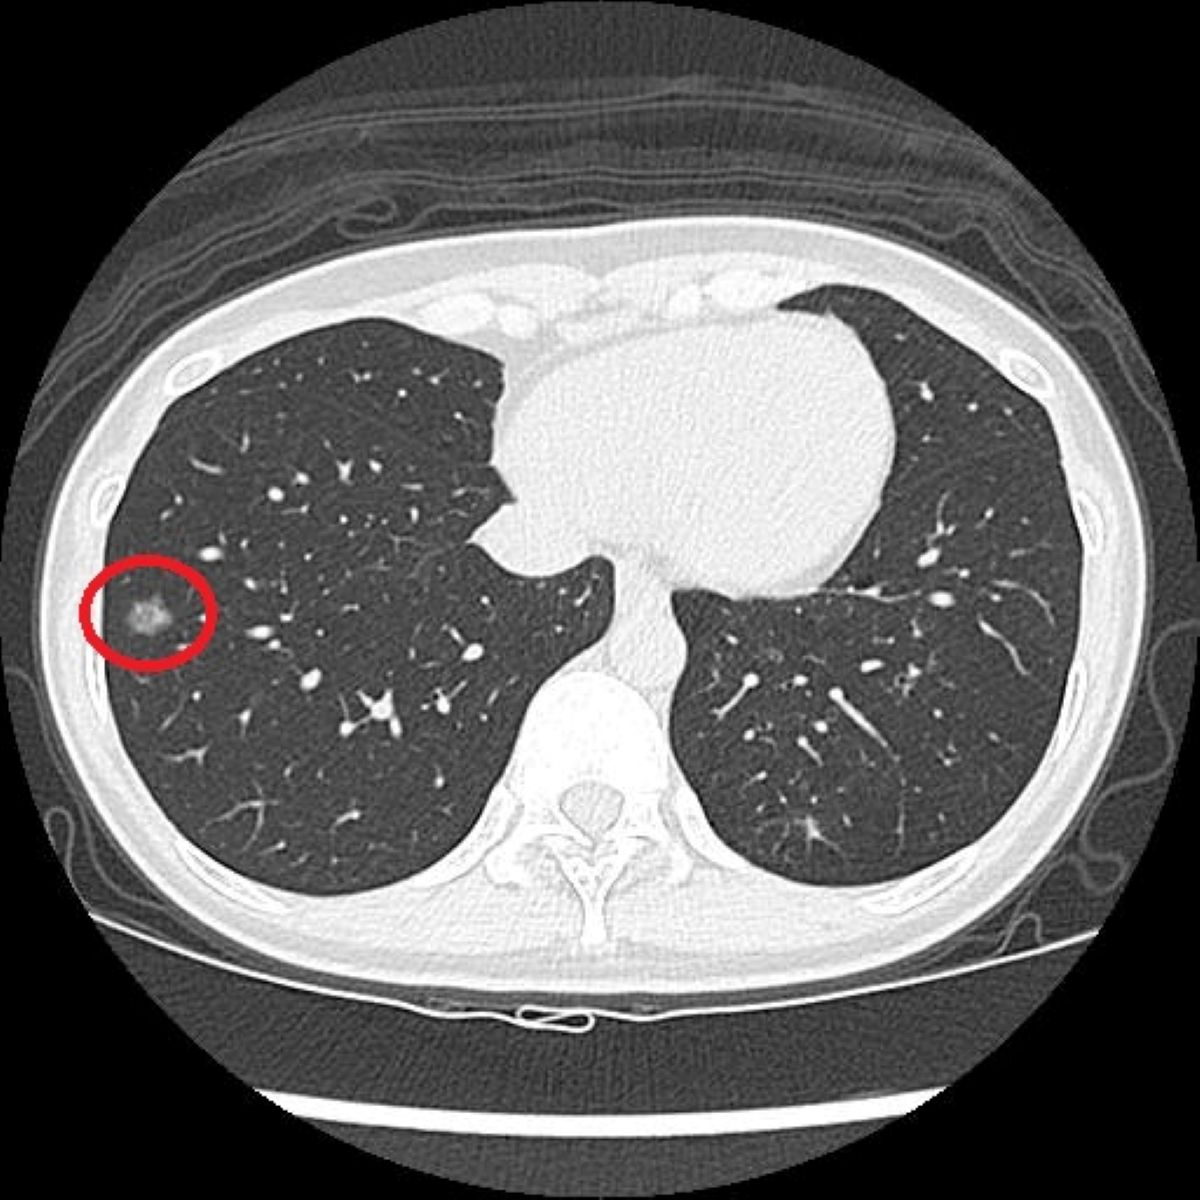

過去有長期吸菸史的41歲陳小姐,在醫療團隊的協助下戒菸近兩年,因符合政府公費「低劑量電腦斷層(LDCT)」篩檢條件,她依建議就醫檢查,卻意外發現右肺有一顆約1.2公分的毛玻璃結節,被轉診至胸腔外科門診,經單孔胸腔鏡微創手術切除病灶,術後病理檢查確診為肺腺癌第1期,目前定期回診追蹤中。

洪嘉聰指出,LDCT篩檢是利用比傳統電腦斷層更低的輻射劑量,從多個角度掃描胸腔,重建出清晰的橫切面和立體影像,有助於偵測肺部的微小結節。相較於傳統胸部X光只有少數約百分之7的受檢者會出現疑似異常影像,LDCT能使初次篩檢的陽性比例提升至約百分之23至24,大幅增加早期病灶被發現的機會。